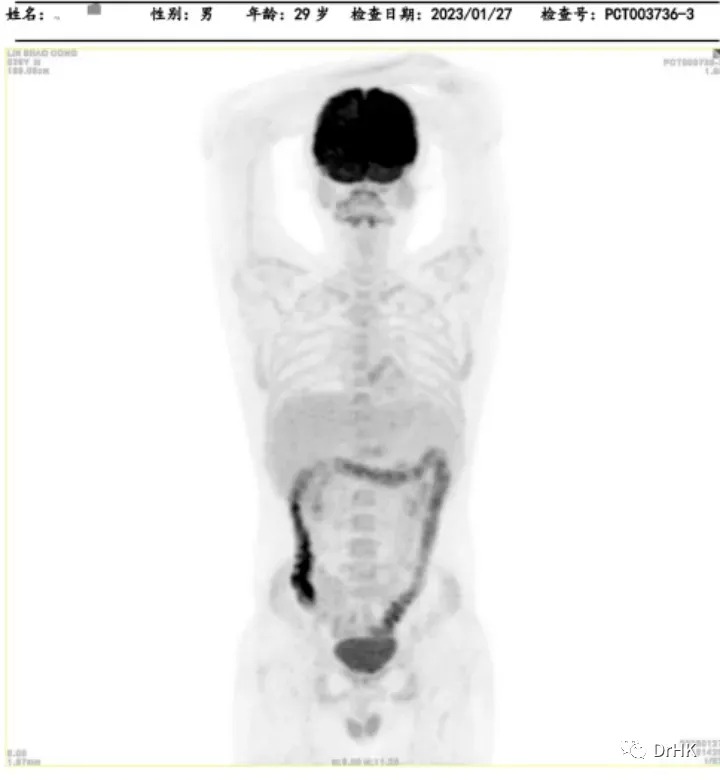

PET-CT

Deauville score: 5 points

Liver involvement: A lesion measuring approximately 3.2×2.6×3.7 cm, with a maximum SUV value of 22.4

Brain: Slightly low-density areas in the deep right temporal lobe and basal ganglia, suggesting lymphoma involvement based on MRI images

Multiple bone lesions: Bone absorption and destruction changes in multiple sites including the bilateral scapulae, clavicles, ribs, sternum, pelvic bones, and vertebrae. Some areas showed increased bone density, with the left iliac bone being the most prominent

Left gluteus maximus muscle: A lesion measuring approximately 1.2×1.6×1.5 cm, with a maximum SUV of 12.4

Starting from April 2, 2022, the patient was treated with the DA-TEDDi-R regimen combined with targeted therapy (ibrutinib + rituximab + dexamethasone + liposomal doxorubicin + etoposide + temozolomide + long-acting GCS + intrathecal Ara-C) for two cycles. After the treatment, the PET-CT assessment showed complete metabolic remission (the first complete remission since the onset of the disease), with a Deauville score of 2-3. Comparing this with the PET/CT imaging from our center on April 1, 2022, the liver lesion significantly decreased and the high metabolic activity disappeared; the left gluteus maximus lesion also disappeared. There were localized bone resorption and destructive changes in multiple bones (bilateral scapulae, clavicles, ribs, sternum, pelvic bones, and vertebrae), with some areas showing increased bone density, particularly in the left iliac bone. The bone marrow glucose metabolism was diffusely elevated, suggesting reactive changes post-treatment, and we recommended further evaluation with a bone marrow biopsy.

The patient was subsequently followed up regularly, with imaging evaluations completed six months and one year after the transplant. It is gratifying to report that the patient has maintained complete remission throughout this period. The PET images are shown below:

Six-Month Post-Transplant Imaging Evaluation